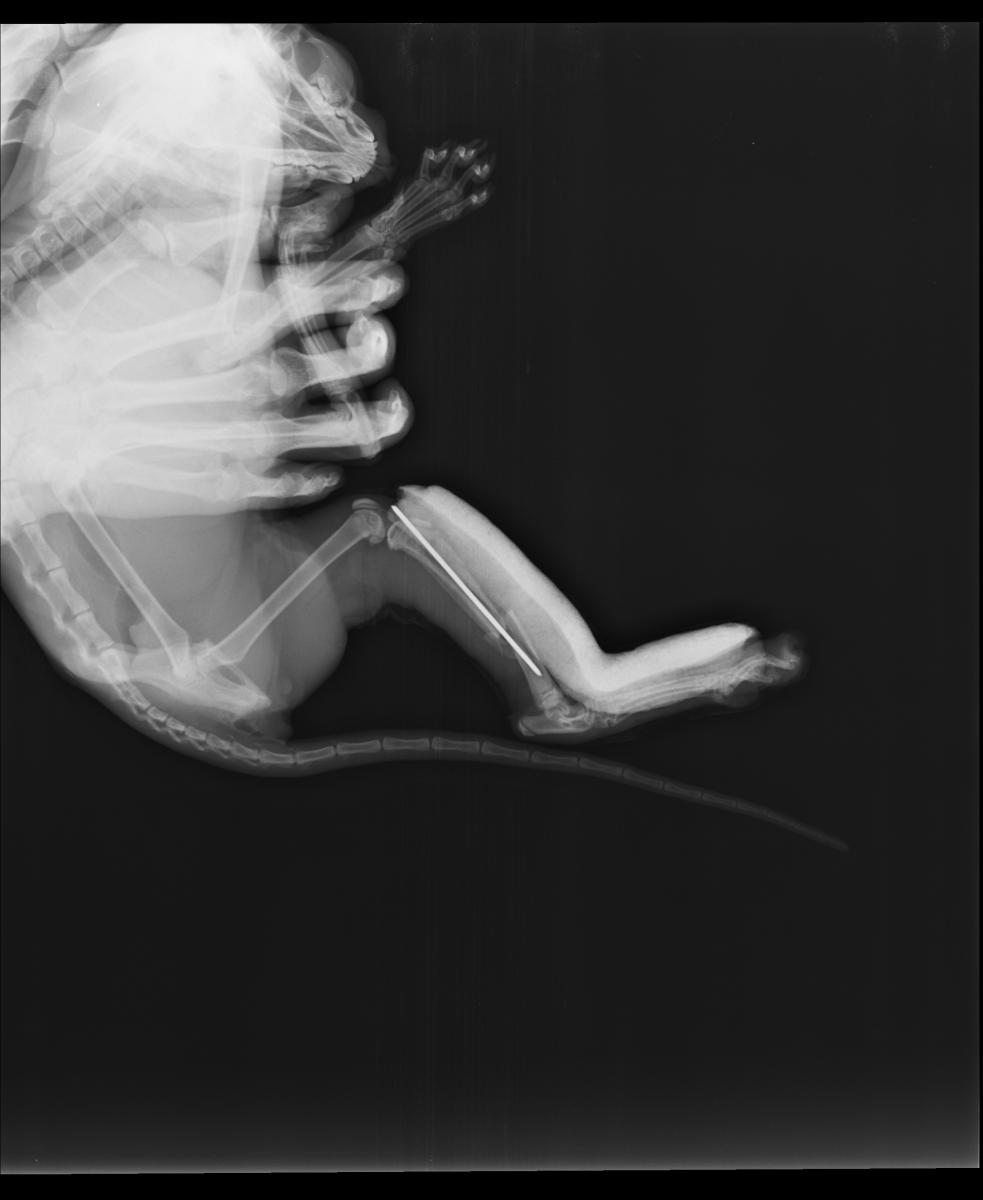

Врач сообщил, что при таком характере перелома, как на снимке выше, остеосинтез желательно проводить накостными пластинами. Он же сказал, что в Подольске с пластинами никто не работает.